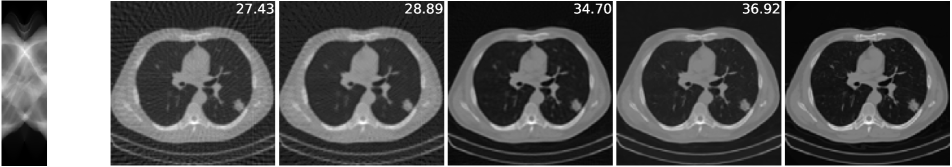

The imaging physics model of X-ray computed tomography (CT) is the discrete radon transform. The physics model is the radon transformation where 50 views (angles) are uniformly subsampled to generate the sparse-view sinograms (observations) . The Filtered back projection (FBP) function, i.e. iradon, is used to approximate . In this task, we exploit the invariance of the CT images to rotations222It is worth noting that shift invariance is not useful for the CT case, as the forward operator is shift invariant itself (see Corollary 1)., and is the group of rotations by degree (=360). We use the CT100 dataset [33], a public real CT clinic dataset which comprises 100 real in-vivo CT images collected from the cancer imaging archive333https://wiki.cancerimagingarchive.net/display/Public/TCGA-LUAD which consist of the middle slice of CT images taken from 69 different patients. The CT images are resized to pixels and we then apply the radon function on them to generate the -views sinograms. We used the first 90 sinograms for training while the remaining 10 sinograms for testing. Note in this task, the supervised trained residual U-Net is just the FBPConvNet proposed in [12] which has been demonstrated to be very effective in supervised learning for sparse-view CT image reconstruction. We train our model with equivariance strength (see SM for more results and the equivariance strength effect). using the sinograms alone while the FBPConvNet is trained with the ground truth pairs .

A qualitative comparison is presented in Figure 4. The sparse-view FBP contains the line artifacts. Both the FBPConvNet and our methods significantly reduce these artifacts, giving visually indistinguishable results. Figure 5 shows the value of PSNR of reconstruction on the training measurements and test measurements and we have the following observations: (i) We would naturally expect the network trained with ground truth data to perform the best. However, we note that the equivariant test error is almost as good despite having no access to ground truth images and only learning on the sparse sinogram data. Furthermore the EI solution is about 7 dB better than the FBP, clearly demonstrating the correct learning of the null space component of the image. (ii) We note that there is a significant gap between training and test error for the FBPConvNet, suggesting that the network may be overfitting. We do not observe this in the EI learning. This can be explained by the fact that the EI constrains the network to a much small class of functions (those that are equivariant on the data) and thus can be expected to have better generalization properties.

We also compared the EI with its adversarial extension in (7) and the supervised learning regularized by equivariance objective. The quantitative results are given in table 1 below. First, MC learning obtains a small improvement in performance over FBP which may be attributable to the fact that FBP is only an approximation to . Alternatively it may be due to the inductive bias of the neural network architecture [34]. Second, the adversarial extension provides a slight improvement to EI and similarly the EI regularization helps the vanilla supervised learning obtain a further 0.6 dB improvement. These results suggest that it is indeed possible to learn to reconstruct challenging inverse problems with only access to measurement data.

| FBP | MC | EI | Sup | |||

|---|---|---|---|---|---|---|

| 50-views CT | 30.24 | 31.01 | 36.94 | 36.96 | 38.17 | 38.79 |